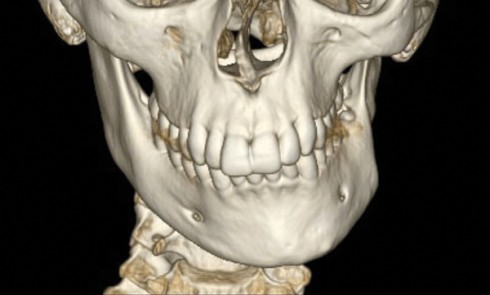

Diagnostic (fig. 1 à 3) Sylvie se présente à l’âge de 15 ans avec une classe III squelettique (ANB -7,6°) d’origine maxillaire...

Diagnostic synthétique Analyse esthétique : la patiente présente une asymétrie faciale (fig. 1a et b) associée à un profil convexe. Son...